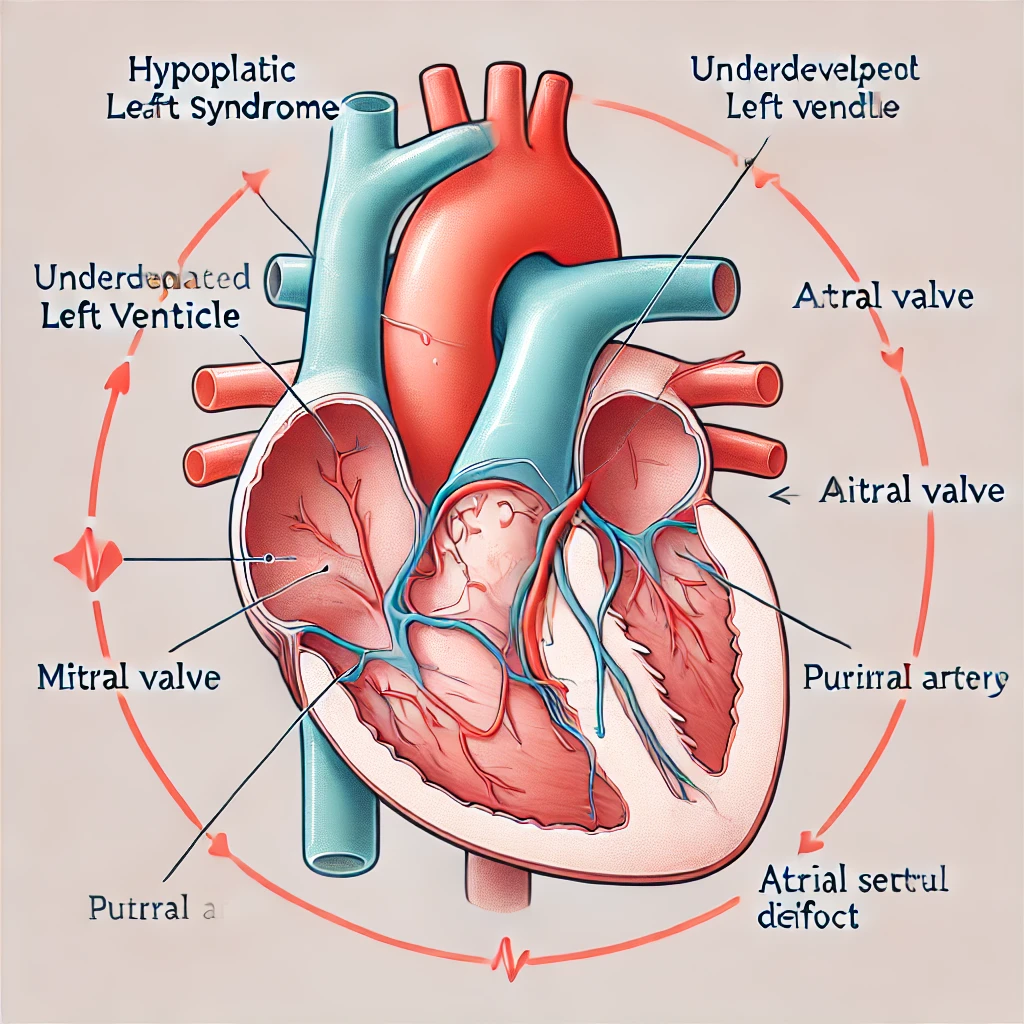

نغطي كل التخصصات الطبية

استیعاب کافة الحالات الطبیة لشمولیة التخصصات

مقالات طبية من مساهمات الأطباء